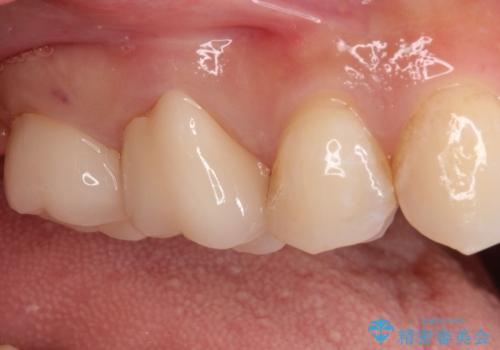

- 奥歯がかけたことを主訴に来院されました。

オールセラミッククラウンにて修復治療を行っております。

歯の破折強度を高めるためにクラウンによる修復を希望され、治療を行っております。